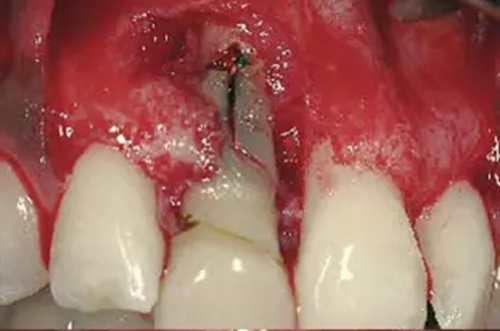

圖2、翻開全厚瓣可見明顯的牙根縱裂,唇側(cè)骨板2/3受到累及而缺損。

圖6、前庭溝半圓形切口,翻瓣后暴露左側(cè)和右側(cè)的骨缺損。

圖7、去除了肉芽組織和根尖感染組織,仔細(xì)沖洗后,可見雙側(cè)拔牙窩唇側(cè)骨壁有大面積缺損。